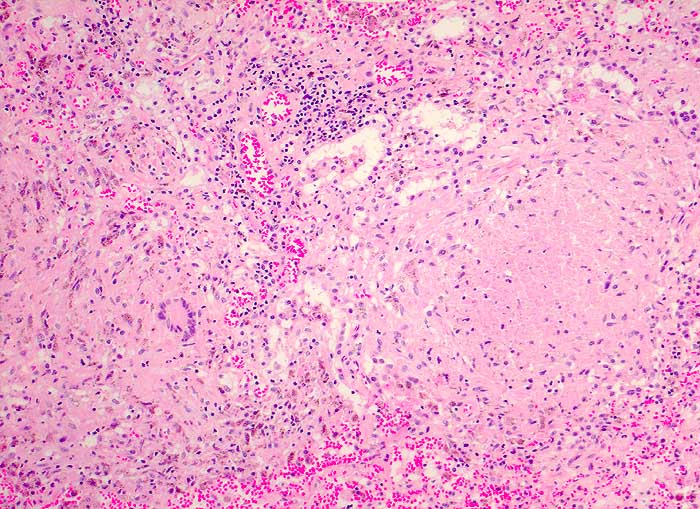

Tuberkulose

Entzündung infektiös

Lymphknoten, Kopf-cervikal

Verkäsende Granulome mit Langhansriesenzellen.

Autopsiebefunde: Miliare

Streuherde in Lunge, Milz (Dm bis 4mm), Nieren, Nebennieren, Ileum

terminale und Zoekum (Tuberkulosepsis) mit Nachweis säurefester

Stäbchen. Lymphknotentuberkulose zervikal beidseits (Dm bis

2x1cm), peribronchial beidseits, paraaortal abdominal (vor allem

peripankreatisch), mesenterial und ileozökal (Dm bis 2x2cm).

Nachweis von Mycobacterium tuberculosis in Abstrich von Milz und

Lunge sowie in der broncho-alveolären Lavage 2 Wochen vor dem Tod. Käsige Pneumonie beider Lungen. Fibrinöse

Pleuritis beidseits.

Generalisierte Lymphadenopathie, Stomatitis, HIV positiv.

Während bei immunkompetenten Patienten der Halslymphknotenbefall meist auf einen Primärinfekt im Bereich der Mundhöhle (Typ Bovinus) hindeutet, sind bei HIV Patienten die Lymphknoten wahrscheinlich im Rahmen einer generalisierten hämatogenen und lymphogenen Tuberkulose befallen (Miliartuberkulose).

100